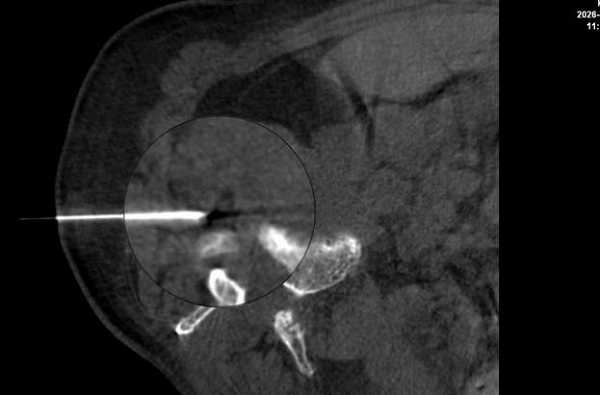

图:细针穿刺至受压神经根,进行精准给药